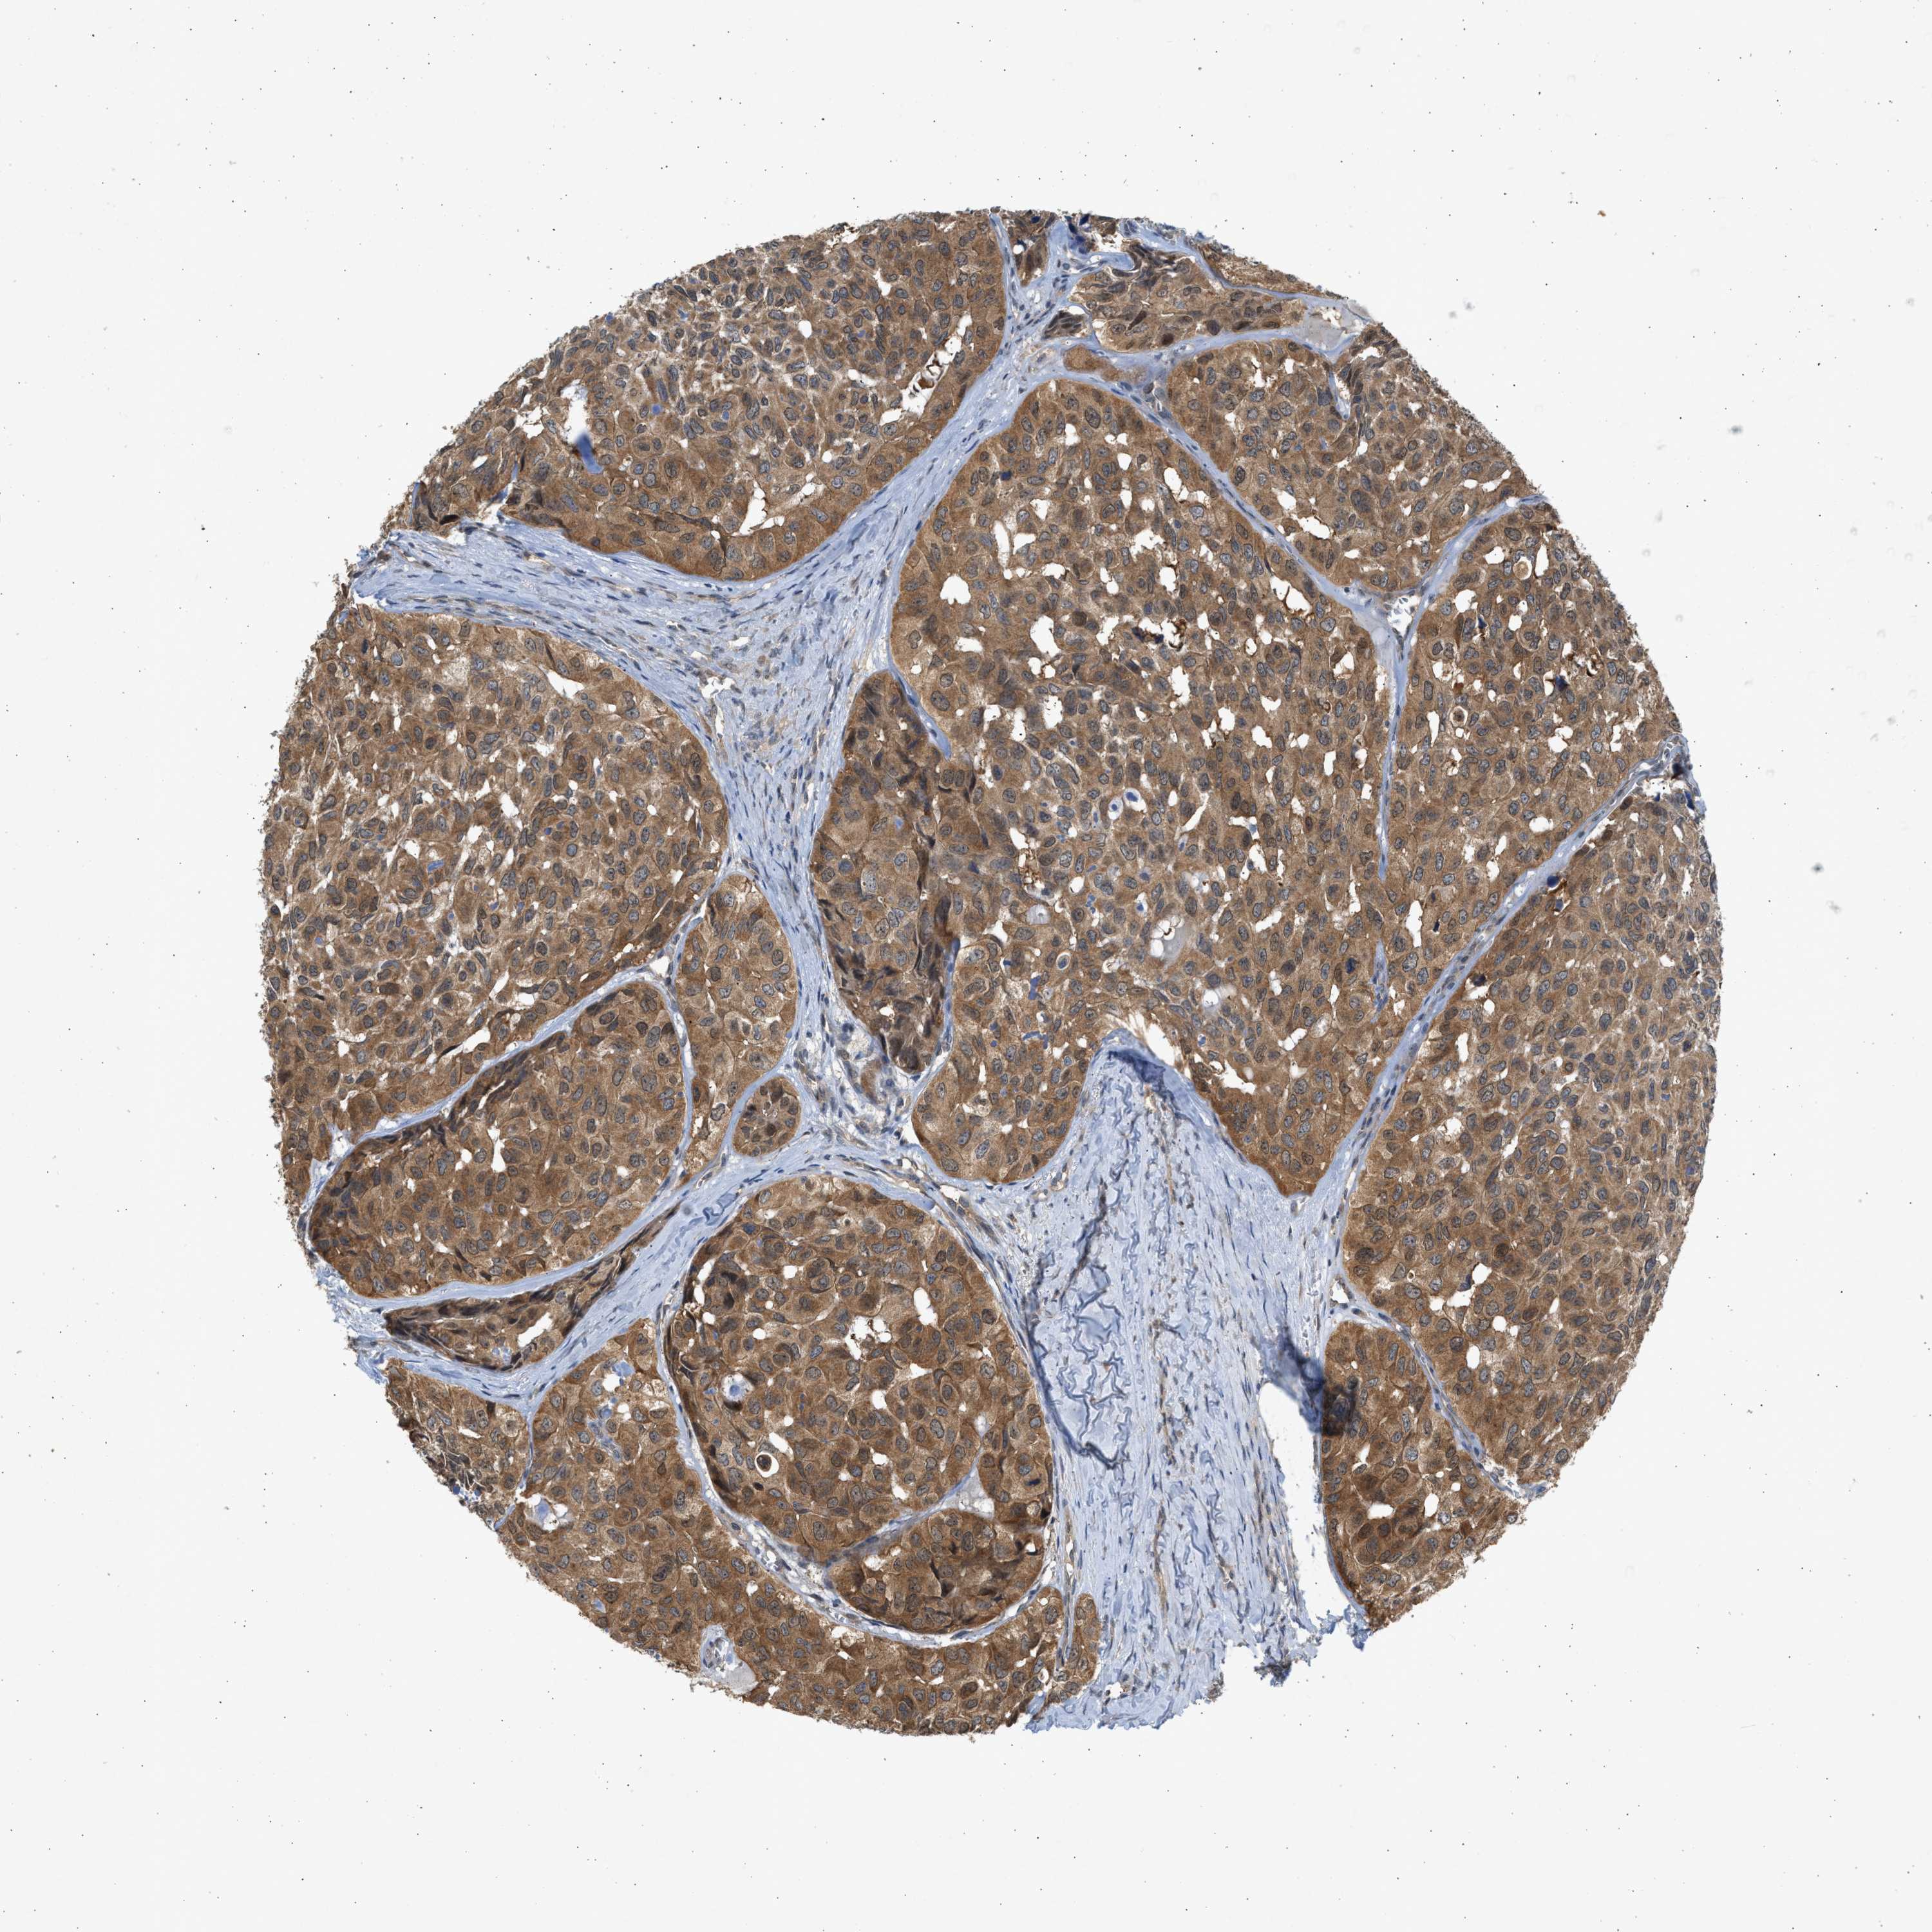

HEAD AND NECK CANCER - Protein expressioni

A mouse-over function shows sample information and annotation data. Click on an image to view it in a full screen mode. Samples can be filtered based on level of antibody staining by selecting one or several of the following categories: high, medium, low and not detected. The assay and annotation is described here.

Note that samples used for immunohistochemistry by the Human Protein Atlas do not correspond to samples in the TCGA dataset.

Antibody stainingi

Antibody staining in the annotated cell types in the current human tissue is reported as not detected, low, medium, or high, based on conventional immunohistochemistry profiling in selected tissues. This score is based on the combination of the staining intensity and fraction of stained cells.

Each image is clickable and will lead to virtual microscopy that enables deeper exploration of all samples and also displays staining intensity scores, fraction scores and subcellular localization as well as patient and tissue information for each sample.

Antibody CAB018561

Staining

High

Medium

Low

Not detected

Intensity

Strong

Moderate

Weak

Negative

Quantity

>75%

75%-25%

<25%

None

Location

Nuclear

Cytoplasmic/membranous

Cytoplasmic/membranous,nuclear

Squamous cell carcinoma, NOS

Squamous cell carcinoma, metastatic, NOS

Adenocarcinoma, NOS